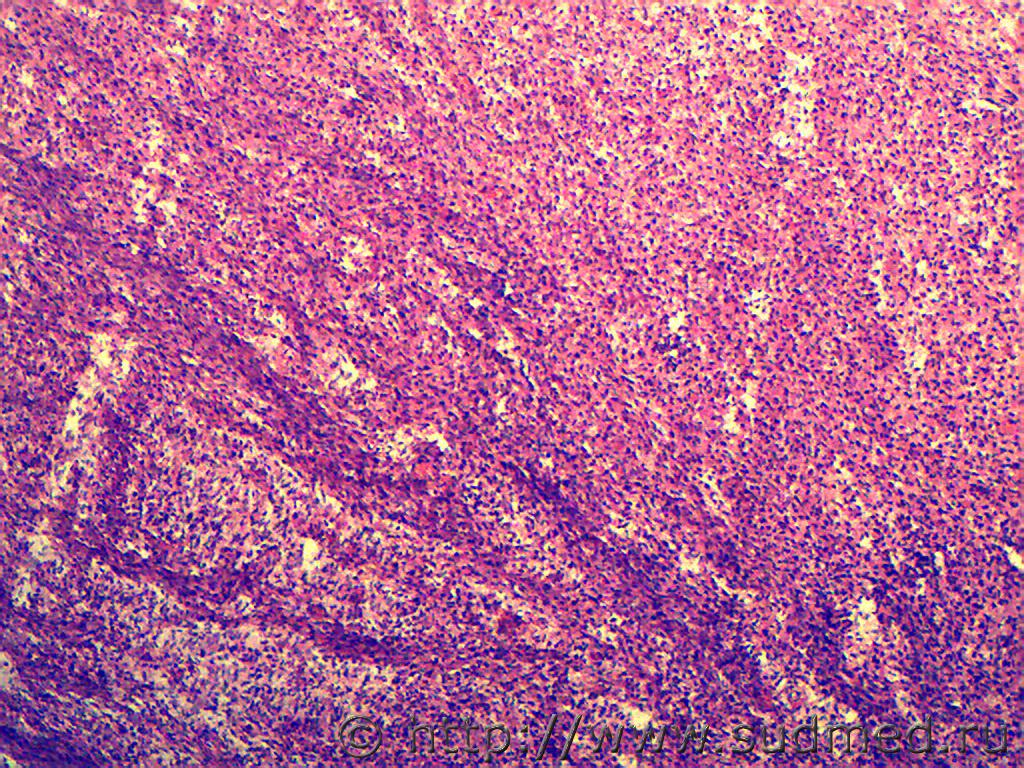

Первые две: ганглионеврома надпочечника (гистологич.находка, случай ДТП)